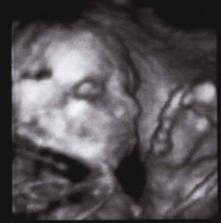

16.9.2008 jsme byli na 3D UTZ byla to nádhera...máme DVD a několik foteček Kubíčka...má už 710 g a měří 30 cm..pořad je to stydlín a nechtěl se nám pořádně ukázat, ale něco málo se paní doktorce podařilo nafotit...hlavně že je všechno v pořádku a Kubík se má čile k světu......